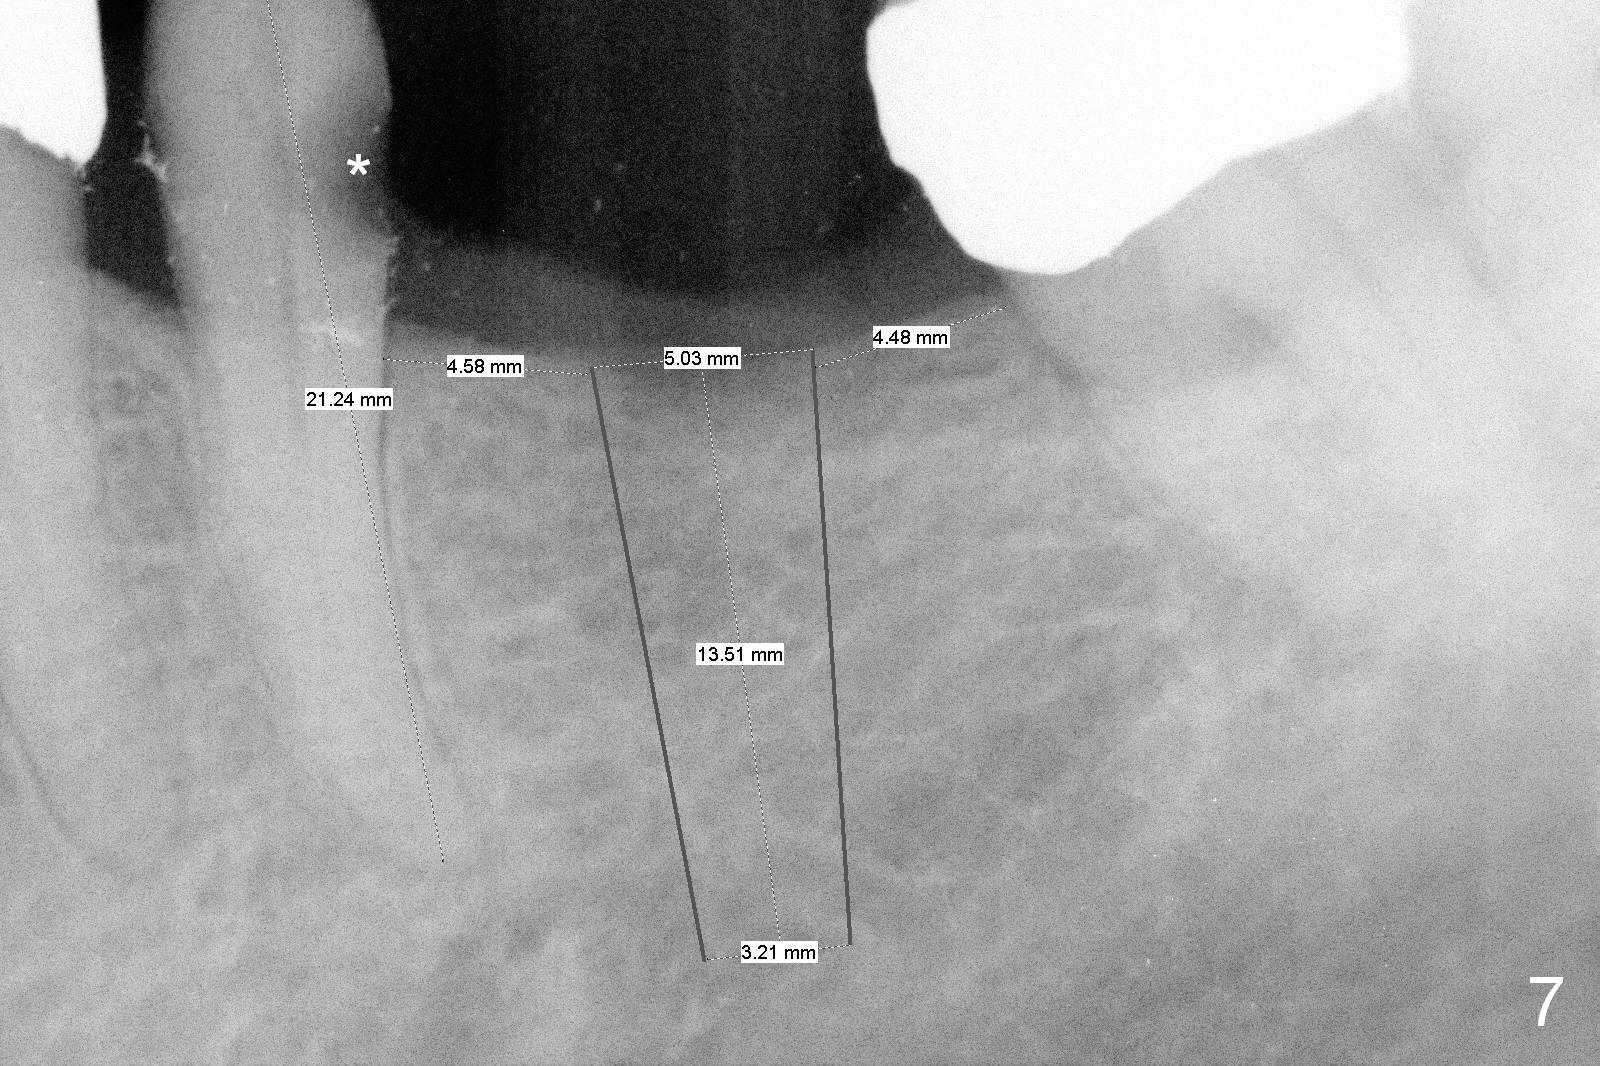

Because of pain, the bridge has been removed partially.  Caries in the tooth #20 (Fig.7 *) is confirmed; root canal therapy has been done.  With bone expansion, the bone level implant can be placed at the crest.  That is, it can be longer (Fig.7: 13.5 mm) than the one placed subcrestally (Fig.2: 10 mm).